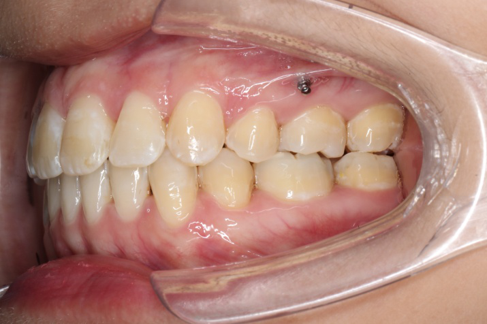

• 磨牙,尖牙I类关系,中线齐

IntraoralExamination(2016-08.31,Wu)

1.第0个月:2016.10.31 ◆ 初戴,0.013cu-niti

2016.10.31  初戴,0.013cu-niti2017.1.13  上颌加TPA,U56间斜形植入韩国庆北1312-08种植钉,上下0.16cu-niti